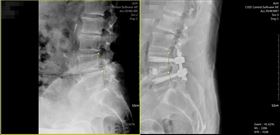

電腦導航微創治療脊椎滑脫 隔天下床行走

北部65歲王姓老翁因脊椎退化造成腰痠背痛,痠麻脹痛感...

婦人腳痠痛6年 一檢查才知龍骨跑掉

台中64歲辛女士常感到右腳痠,終日躺也不是、坐也不是...